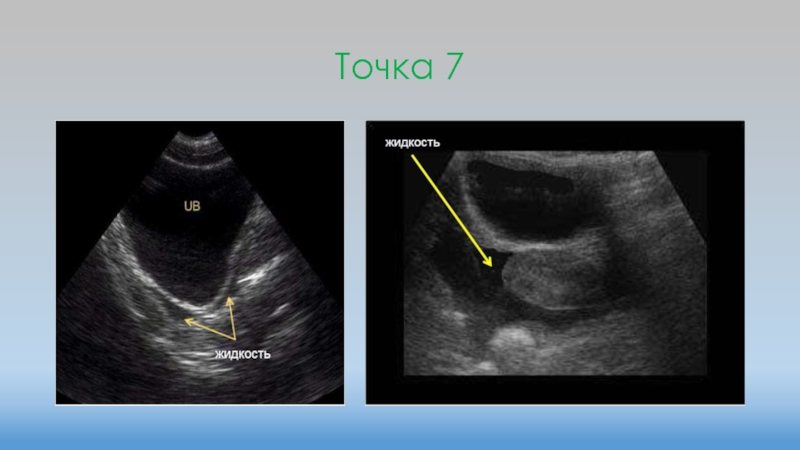

Слайд 23Точка 7

Точка 7

Слайд 24Точка 7